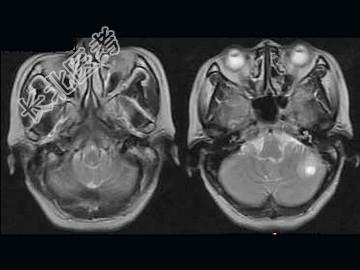

- 单项选择题女,52岁, 头晕2周,MRI检查如图, 最可能的诊断为 ( )

A、多发结核球

B、胶质瘤

C、囊性星形细胞瘤

D、脑内多发转移瘤

E、囊性淋巴瘤